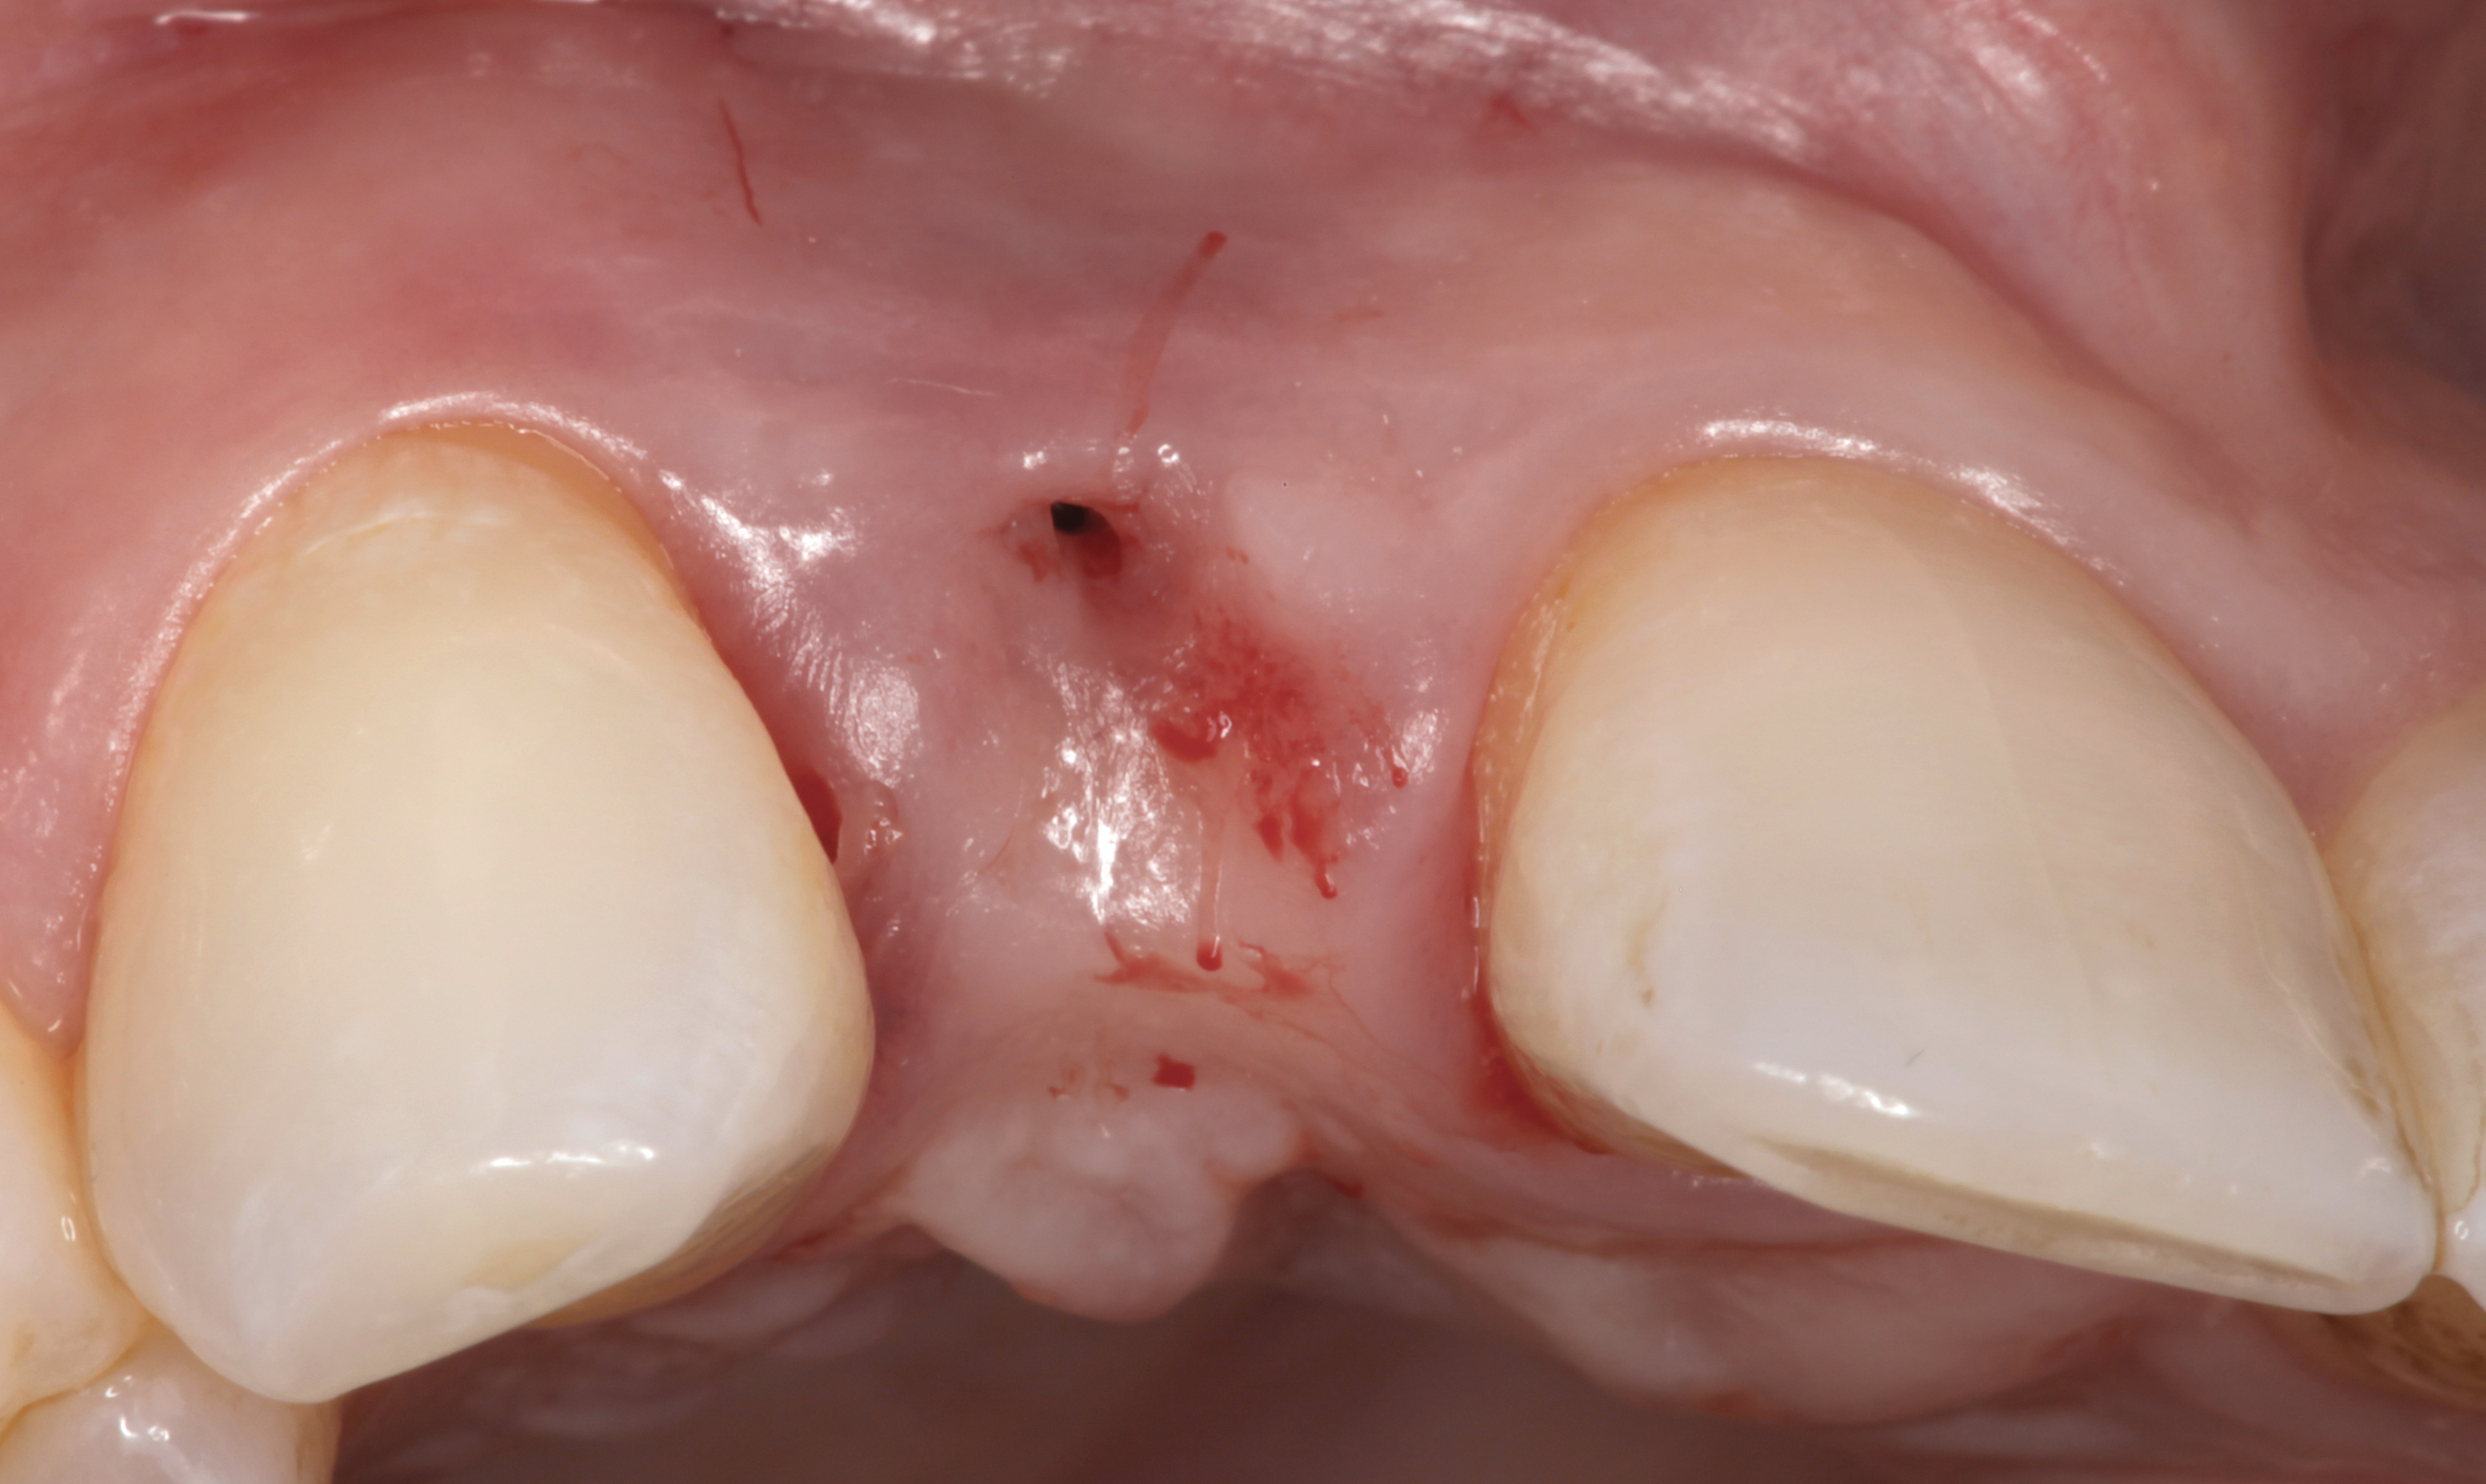

The following case report provides an example of this case scenario: A 28-year-old white female patient presented with her maxillary right lateral incisor significantly longer than the contralateral tooth following restoration of an existing crown that was 10 years old (Figure 3). The patient was dissatisfied with the esthetic appearance of the restoration due to the increased length, recession of the gingival tissues, and discoloration of the surrounding mucosa (Figure 4). Similar to case scenario No. 1, the first step in treatment was to decoronate the healthy implant by placing a flat surgical cover screw and employing a provisional resin-bonded-retained (RBR) prosthesis as a transitional fixed restoration (Figure 5 and Figure 6). The gingival augmentation in situ was allowed to take place for 2 to 3 weeks and was evaluated after that time (Figure 7).

Fig 3. A patient presented with a high smile line and midfacial recession of the maxillary right lateral incisor as evidenced by the increased tooth length compared with the contralateral lateral incisor.

Fig 4. Intraoral view of tooth No. 7 with the gingival zenith more apical than the adjacent central incisor and canine tooth.

Fig 5. A surgical cover screw was placed onto the implant in order to achieve gingival augmentation in situ prior to a secondary soft-tissue procedure.

Fig 6. A transitional resin-bonded-retained dental prosthesis was used to replace tooth No. 7.

Fig 7. The gingiva was allowed to grow over the cover screw for a 2- to 3-week period. The soft-tissue shape was still deficient and would require a secondary augmentation procedure.